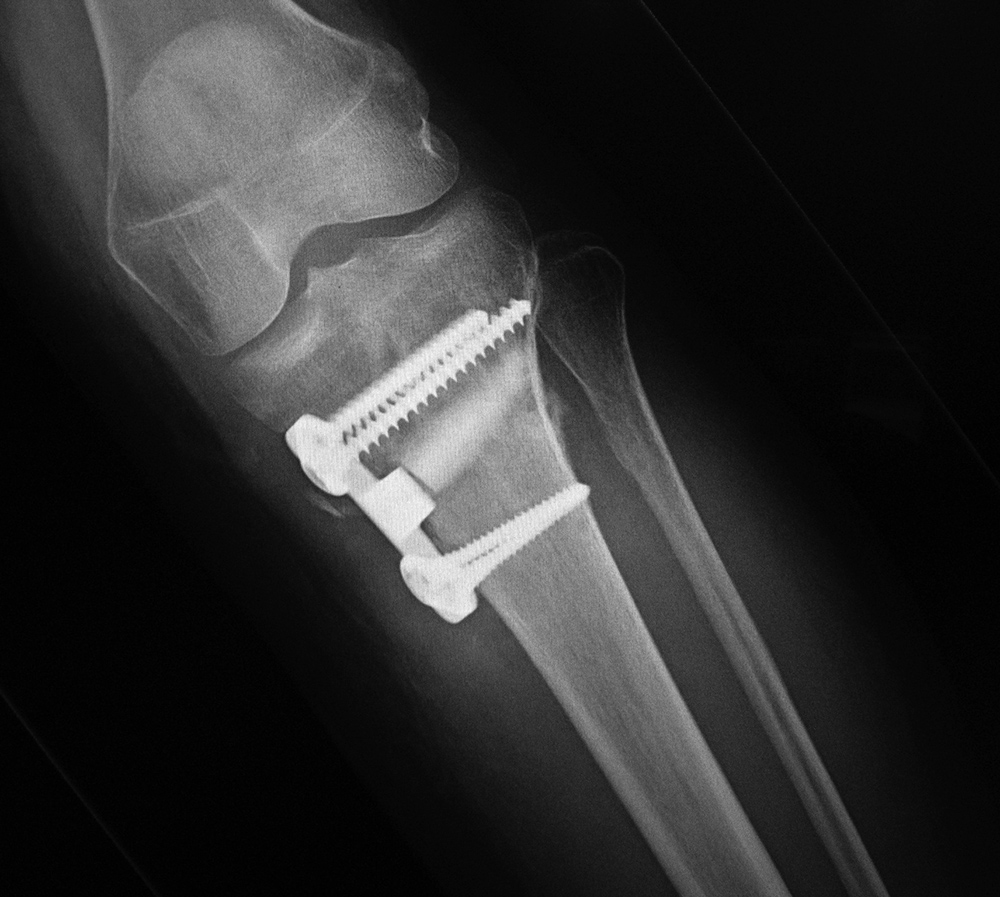

43 year-old man with comminuted right tibia and fibula fractures as well as extensive bone loss and soft tissue injury. A tibial intramedullary nail with proximal and distal locking screws is present as well as multiple rounded bony allografts. There are also large skin staples.